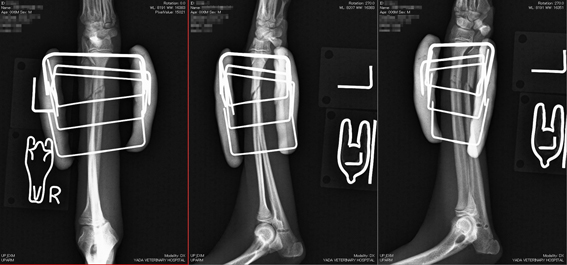

写真(上):手術中のX線写真

手術は、患部を切開することなく実施しています。(完全非開創手術)

創外固定ピンを刺入する部位の皮膚にレーザーで小さな穴を開けるだけで、骨折部を切開することなく整復固定が可能です。患者の負担は、軽くなります。